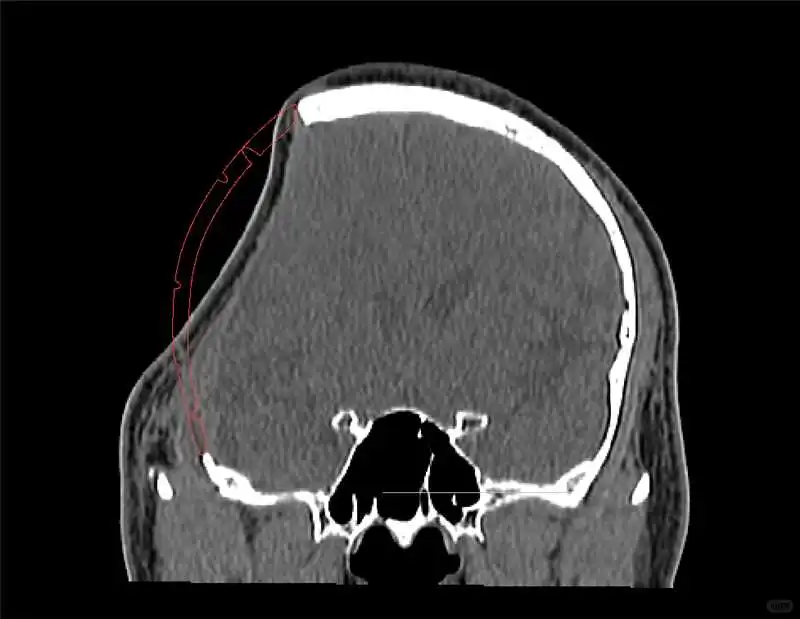

2️⃣中期(1-6周)通过CT评估假体位置,逐步恢复日常活动但避免剧烈运动,密切观察神经功能变化;